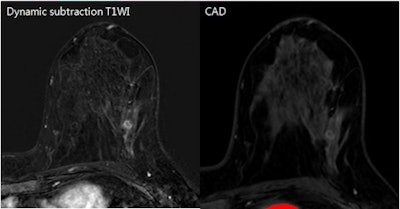

False-negative breast MRI CAD result in patient with an approximately 1-cm metaplastic carcinoma in her left breast. Contrast-enhanced subtraction image (left) shows an irregular rim-enhancing mass, suggesting a typical malignant-looking mass. MRI CAD results (right) did not show a color map, however. The patient had a low Ki-67 percentage. Images courtesy of Dr. Seon Hyeong Choi.After 32 cases were excluded due to conditions such as no residual cancer after excision or chemotherapy, no operation after excision, no IHC results, and carcinomas of unknown primary origin, the remaining 324 patients with 327 histologically proven breast cancers were included in the study.